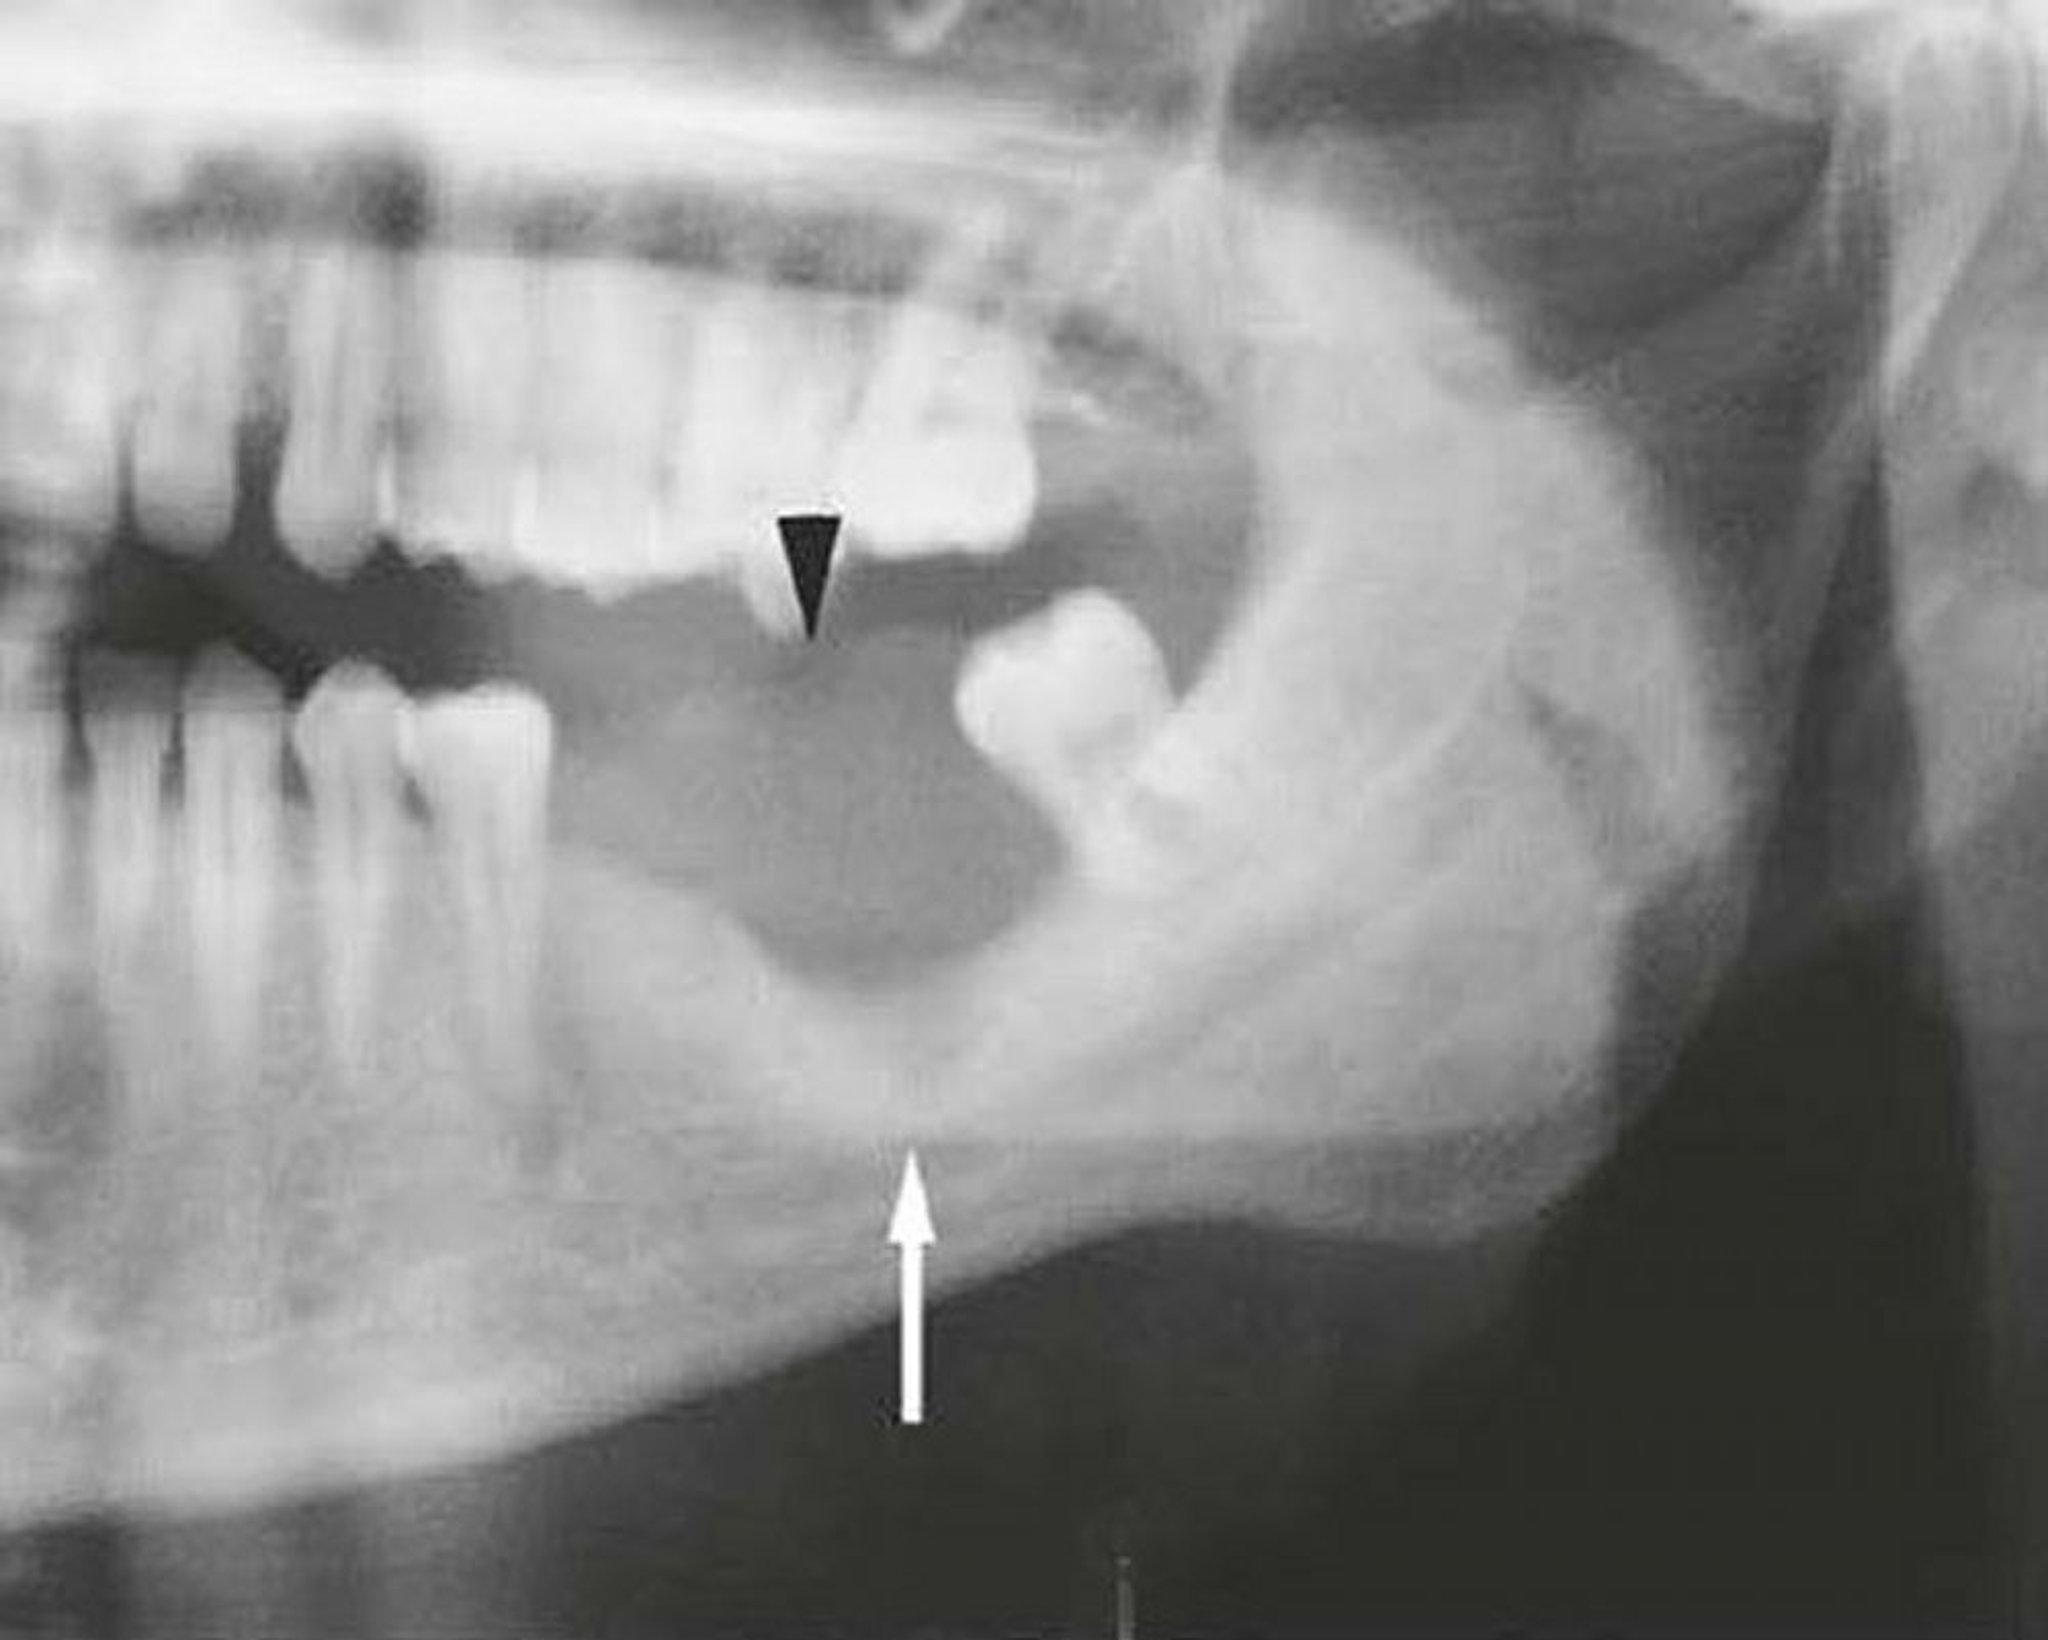

Esta imagen de una mandíbula invadida por un carcinoma epidermoide muestra un tumor de partes blandas (punta de flecha) y destrucción ósea (flecha).